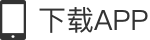

18岁的小强刚刚参加完高考,对未来的生活充满憧憬,可是最近三个月,右侧面颊部渐大的隆起让这个开朗的大男孩不禁开始了“颜值焦虑”。带着紧张的心情,家人陪同小强来到了湖南省第二人民医院(省脑科医院)耳鼻喉头颈外科就诊,门诊余丽亚副主任医师对患者进行了仔细的检查后,诊断为上颌窦含牙囊肿。(见图)

根据小强的检查结果(见图),右侧上颌窦已被囊肿及囊液填的满满当当,上颌窦原本坚实的骨质被囊肿压迫变薄甚至吸收。只剩下周围一层薄薄的皮质骨,在右侧上颌骨接近颧骨的位置,卡着一颗明晃晃的牙齿。综合分析后,余丽亚副主任医师建议患者尽快办理出院,行手术治疗。

上颌窦含牙囊肿一旦膨大,通常采用外科手术诊疗,术前完善CT等检查对明确肿物范围、位置及毗邻关系,对制定精准个体化手术诊疗方案相当重要。